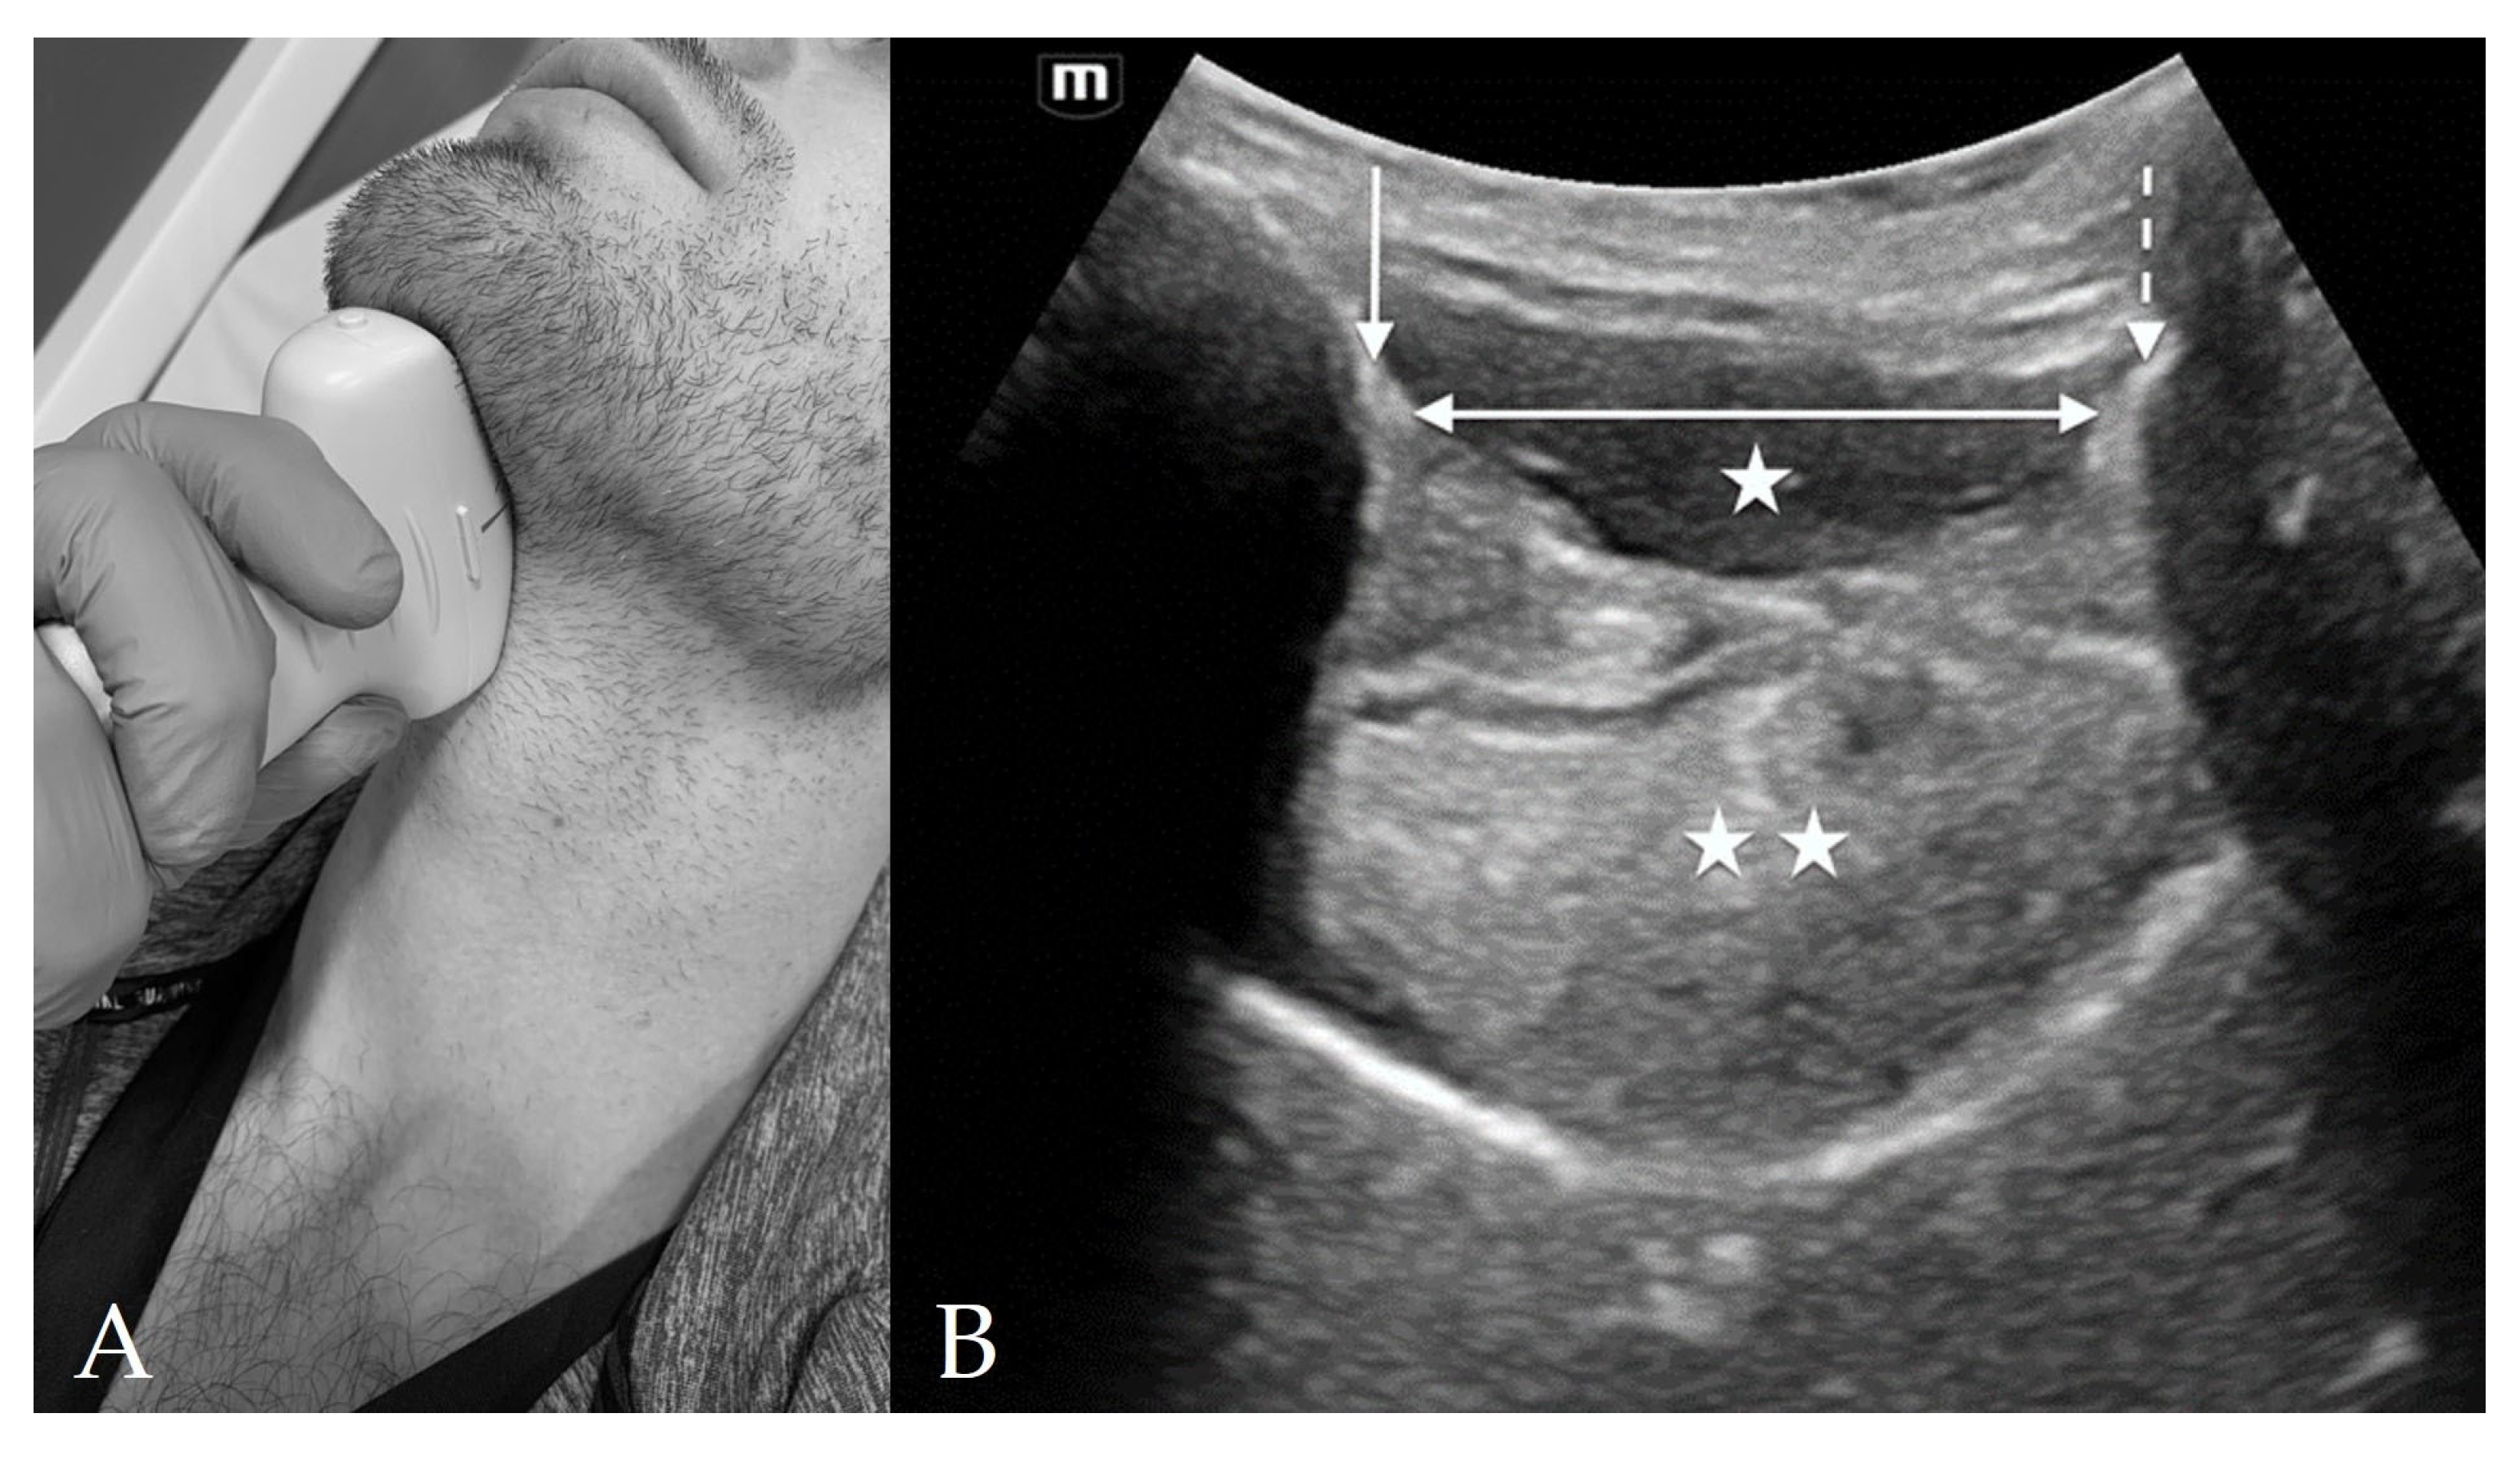

4.1. Suprahyoid View